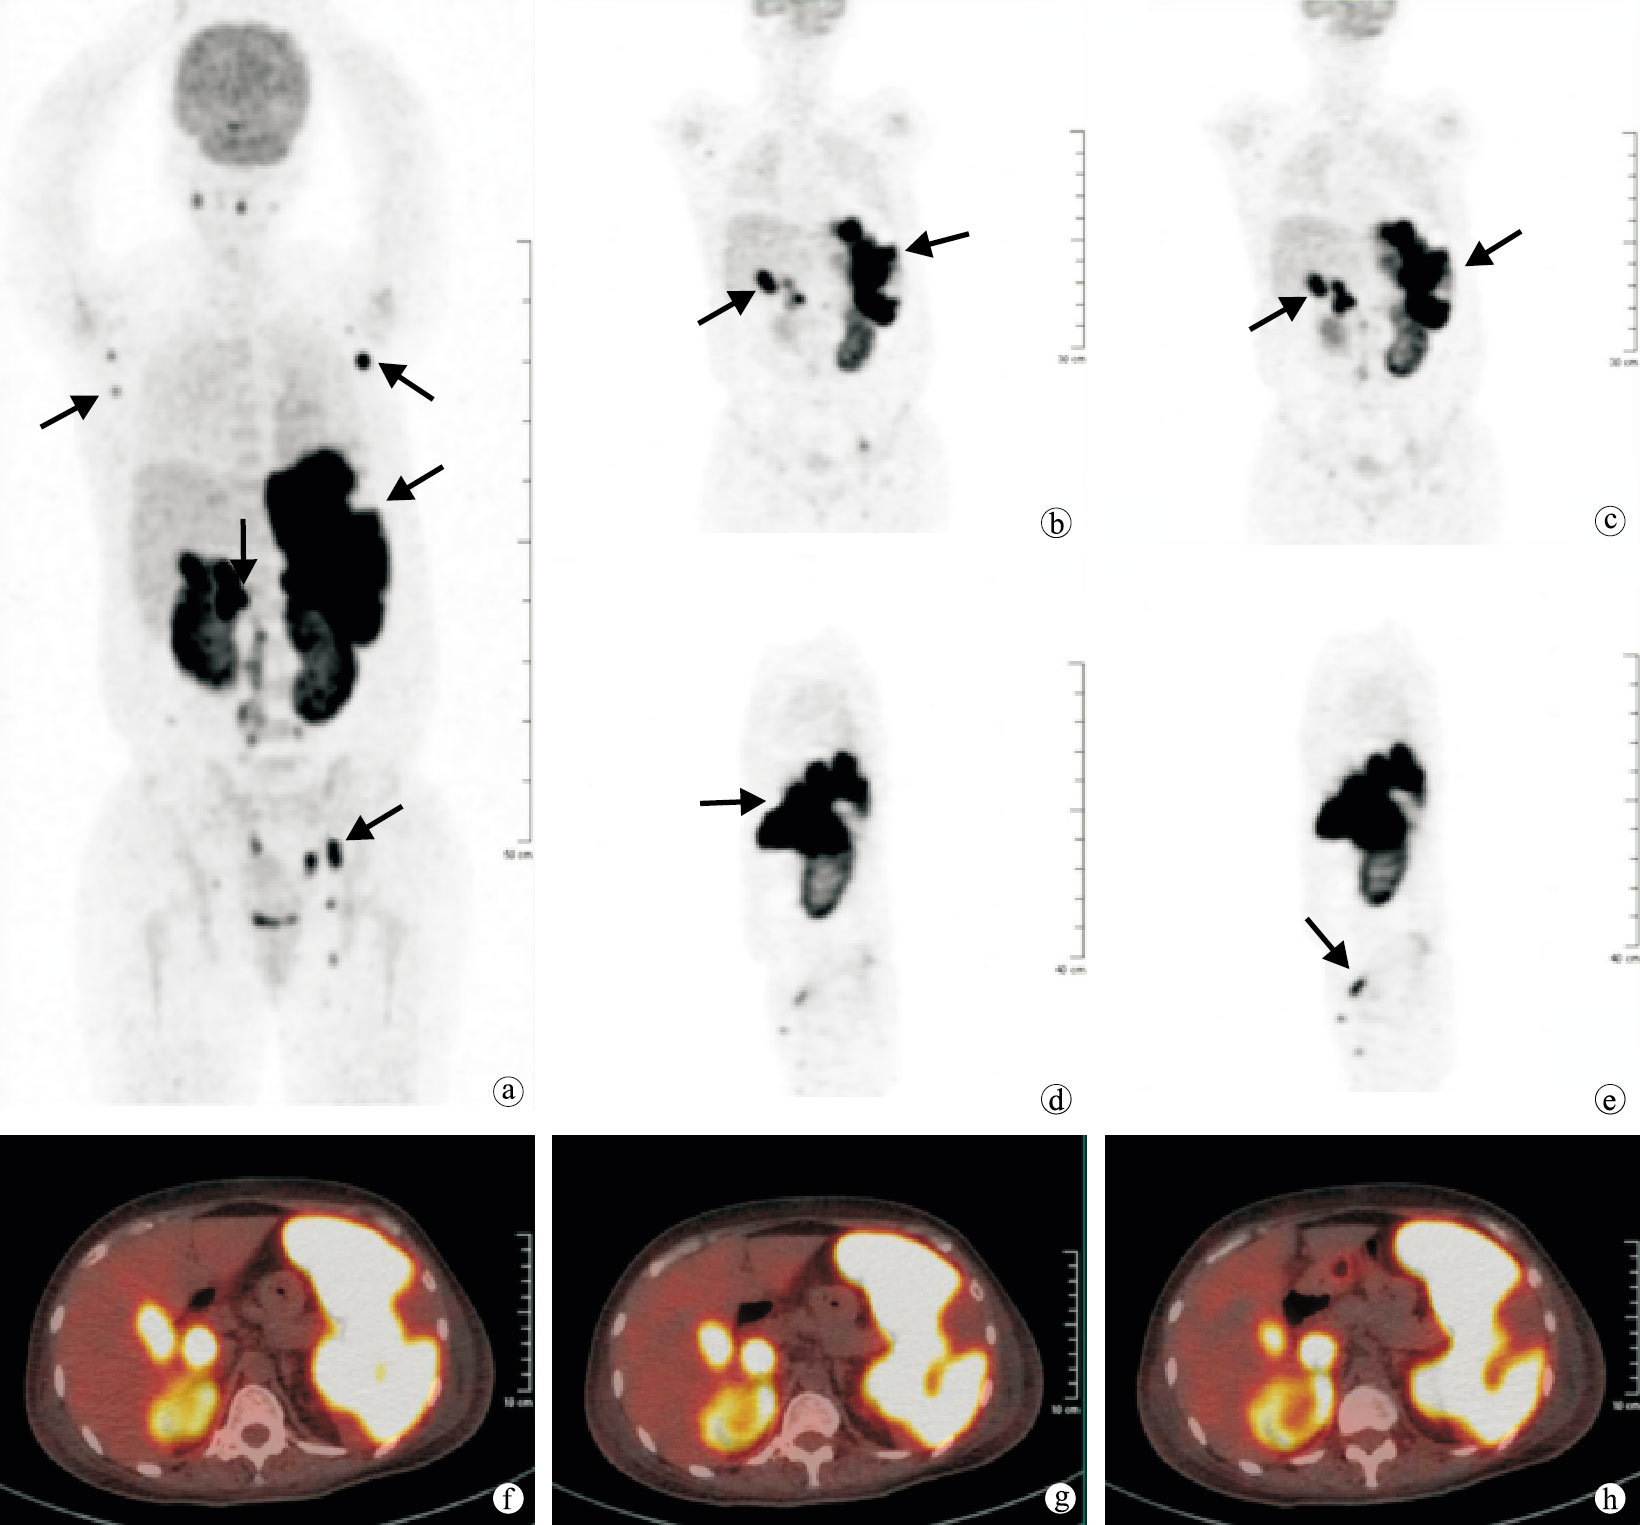

另有3例明確診斷的患者顯像為陰性,其診斷分別為盆腔炎癥、下尿路感染和干燥綜合征各1例。有8例患者為真陰性,雖然18F-FDG PET/CT顯像未得到確定診斷,但顯像至少排除了一些可能病因,所以18F-FDG PET/CT顯像對這類患者的診斷也是有幫助的。18F-FDG PET/CT顯像對25例(78.1%)患者的診斷具有幫助,在尋找FUO病因的靈敏度85.0%,特異度66.7%。典型患者18F-PDG PET/CT圖像見圖 1。

PET/CT圖像發熱1+個月,PET的最大密度投影(a),冠狀位(b、c),矢狀位(d、e)圖顯示雙側腋窩及左側腹股溝淋巴結、膽囊、肝總管、膽總管、脾臟及雙側腎臟攝取18F-FDG增高(黑箭)。PET/CT斷層融合圖像(f~h)示脾臟地圖狀攝取18F-FDG增高

本組中例12患者,主要以發熱、疲乏、食欲不佳及體質量減輕等非特異癥狀就診,住院1周仍未查明發熱原因,18F-FDG PET/CT顯像結果(圖 1)示雙側腋窩淋巴結、肝臟、膽總管、脾臟、雙側腎臟攝取18F-FDG增高,根據顯像結果引導行腋窩淋巴結活檢,病理示非霍奇金淋巴瘤。當淋巴瘤未導致組織器官發生解剖結構改變時或者僅累及深部淋巴結時,在臨床上不易引起重視,其他的影像學檢查中也易漏診這些病灶[10]。18F-FDG PET/CT顯像在對這類淋巴瘤患者的診斷有重要意義。